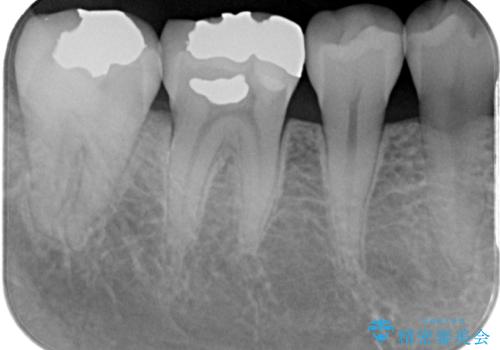

- 当院で矯正後に銀歯が目立つのでやり替えたいと来院された患者様です。銀色の詰め物(メタルインレー)と歯の間に隙間を認め、あまり歯を削りたくないとのことで患者様と相談の結果右下の7番目の歯はセラミックインレー、右下の6番目の歯はメタルインレーが大きいためフルジルコニアクラウンでの治療を行うことになりました。

拡大鏡視野下で、銀色の詰め物(メタルインレー)、保険のプラスチック、虫歯の除去を行い、セラミックインレー、フルジルコニアクラウンに適した形に整えました。

歯と歯の間の虫歯をコンポジットレジンや保険のメタルインレーで治すと段差ができたりして清掃性が悪くなるので、セラミックインレー修復やゴールドインレー修復などの適合の良い詰め物で治療することをオススメします。又、適合の良い詰め物、被せものだと虫歯の再発リスクを低減できます。